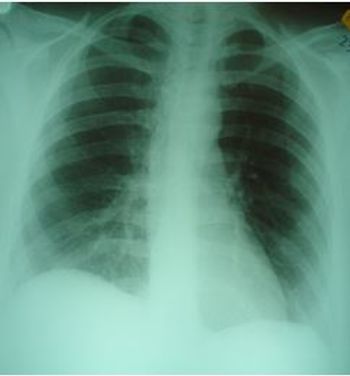

Worsening respiratory symptoms and fatigue of 6 months’ duration brought a 44-year-old woman in for evaluation. Diagnosed with asthma 2 years earlier, she was compliant with, but unresponsive to treatment. Your impressions?